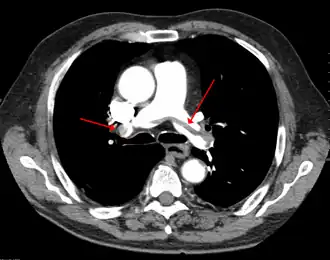

Voor het radiologisch vaststellen maakte men vroeger gebruik van angiografie. Deze methode is echter grotendeels verlaten. Tegenwoordig is de gouden standaard een CT-scan van de borstkas met contrast. Hierbij is de embolie te zien als een contrast-uitsparing: de embolie contrasteert niet met de ribben. Ook een ventilatie-/perfusiescan komt in aanmerking: de ventilatie over het aangedane deel van de long blijft immers normaal, terwijl de perfusie (doorbloeding) afgenomen is).